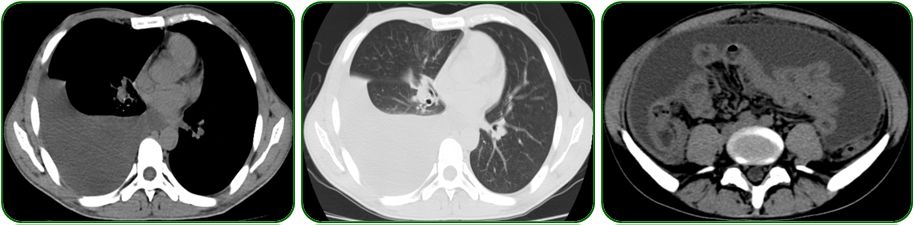

胃镜、肠镜未见异常,如图6;

肺部CT提示双肺纹理增多、左侧胸腔少量积液,如图7a-b;

腹部彩超示腹腔积液,如图7c。

图6 胃镜、肠镜检查

图7 胸部CT及腹部彩超检查